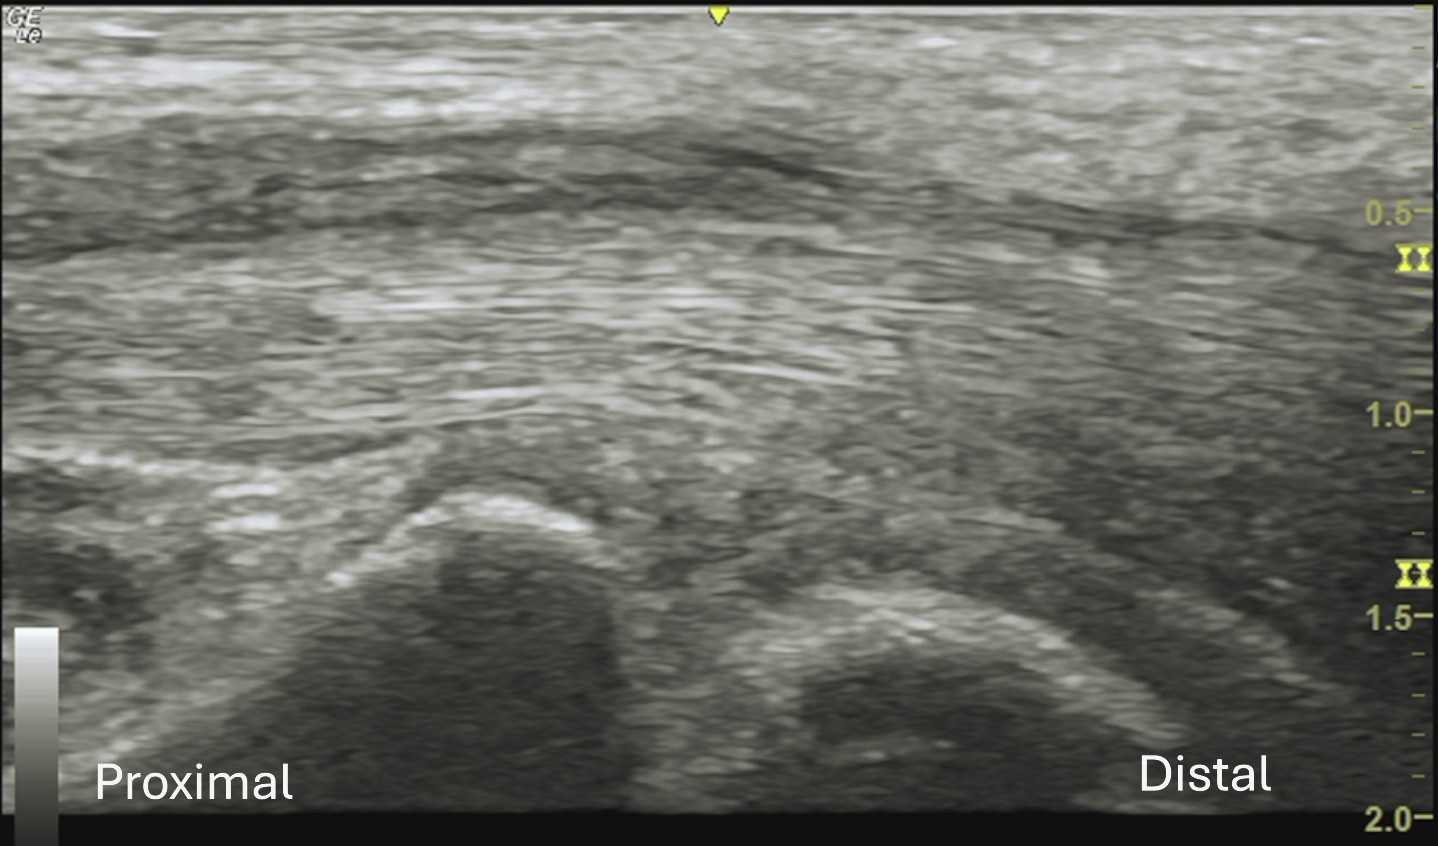

Labeled long axis view of the median nerve at the wrist demonstrating progressive distal tapering of the median nerve within the carpal tunnel, with surrounding homogeneous isoechoic soft tissue.

Unlabeled long axis view of the median nerve at the wrist.